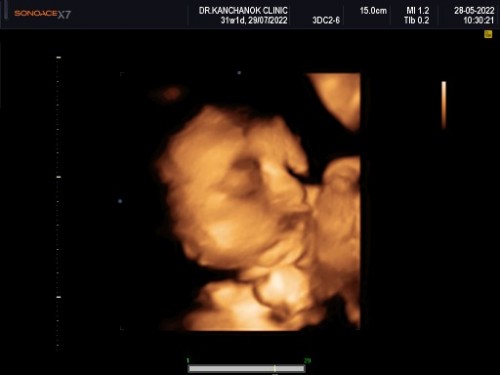

ทำไมดูหน้าลูกแปลกๆไม่กล้าถามหมอหรือในภาพซาวเป็นแบบนี้คะขอดูรูปลูกๆบ้านอื่นหน่อยค่ะ

32w+2dทำไมดูหน้าลูกแปลกๆไม่กล้าถามหมอหรือในภาพซาวเป็นแบบนี้คะขอดูรูปลูกๆบ้านอื่นหน่อยค่ะ

4มิติค่ะ 23วีค

3มิติค่ะ ลองไปซาวด์ดู

ซาวตอน7เดือนค่ะ